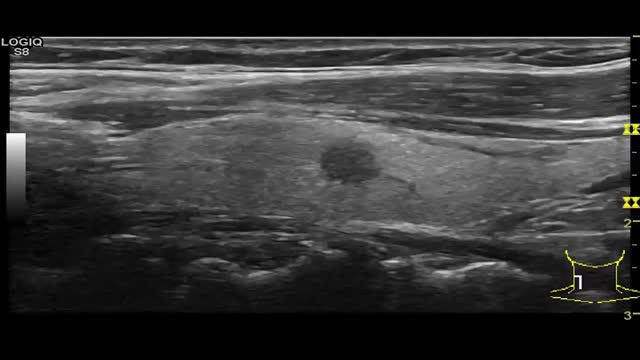

Espongiforme (0 puntos): contiene múltiples componentes microquísticos en su interior. Sugieren benignidad (video 1)

- •

Mixto (1 punto) (video 2)